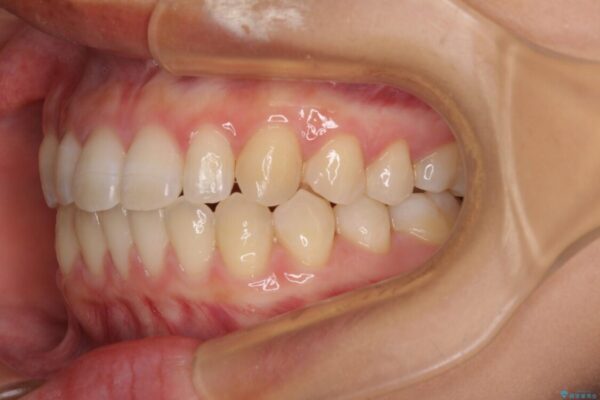

治療後

• 隙間だらけの歯列 インビザラインで改善 治療後画像

空隙歯列(すきっ歯)は、舌の突出癖をある程度改善できたとしても、後戻りにより隙間が開きやすいと言われています。

裏側から細いワイヤーで保定するとともに、睡眠時のマウスピース装着を徹底していただくことで、後戻りを最小限にとどめます。